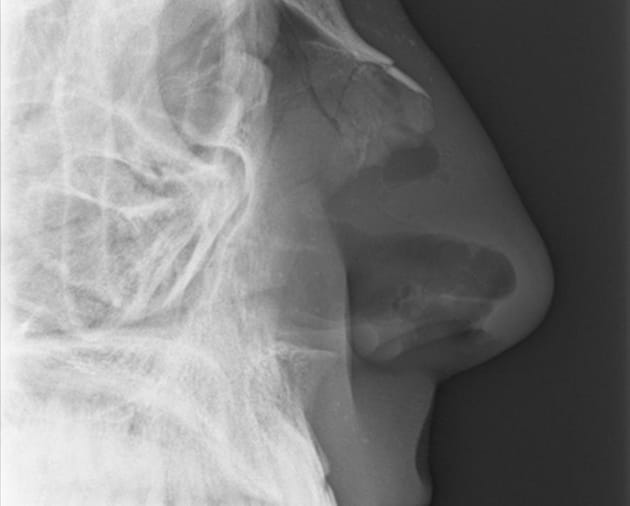

X-ray image courtesy of Willy Nast

They called my name and led me to an examination room. The doctor looked up my nostrils and slid a long cotton swab deep into each cavity to clear the dried blood. My eyes watered. She asked me if my nose had always been curved. She ordered an X-ray.

I followed Jamie, the X-ray technician, to the cool metal room where he would take the images of my face. He carried a springy energy in his legs that that felt somehow familiar. When we reached the X-ray table, he turned and studied my face.

“Left hook?” Jamie asked. Then he took a half-step backward, pointing his shoulder toward me, bent his knees and rocked gently on the balls of his feet—the boxing stance. The very first thing they teach you at a boxing gym.

“I see it,” he said, smiling and cocking his right fist. “It had to be a right hand.” He sat me in a chair next to the table.

“No,” he answered, positioning my head sideways on the X-ray table, as if I were taking a nap in the middle of dinner. “I took a lot of martial arts when I was younger. My brother was a boxer, though.” He aligned the X-ray tube over my head, and stepped behind the protective wall to take the pictures.

It’s not that I fear another injury; that fear has always been there. It’s not the memory of the moment of impact and the crunching sound I heard in my head. It’s not the way the blood tasted in my mouth or the look of the crooked line in Bill’s nose. What haunts me is the way Jamie slid the negative over the soft backlight, and tapped the black and gray image of my skull with his forefinger.

“You had to know,” he said. “Something like this was bound to happen.”